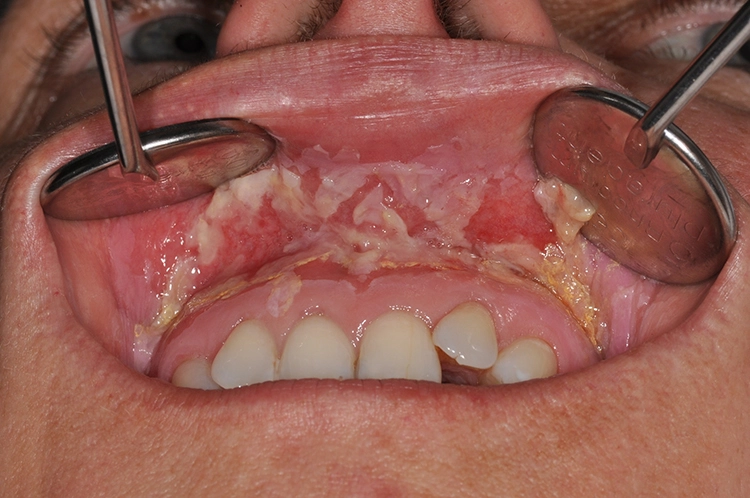

In den nekrotischen Arealen kann dann eine Besiedlung mit ortsständigen Keimen der Mundhöhle zu einer Superinfektion führen. Für die Definition der IORN ist das Fehlen einer antiresorptiven Medikation (Bisphosphonate, Denosumab) in der Anamnese essenziell. Das klinische Leitsymptom der IORN ist die Schleimhautulzeration und der chronisch freiliegende Kieferknochen (Abb. 4).

Prävention und Therapie der infizierten Osteoradionekrose Zur Prophylaxe der IORN gilt es folgende Maßnahmen vor einer geplanten Strahlentherapie im Kopf- und Halsbereich im Rahmen der präradiotherapeutischen Mundhöhlensanierung durchzuführen:

- Entfernung harter und weicher Beläge

- Extraktion avitaler, nicht wurzelkanalbehandelter Zähne und fortgeschritten parodontal geschädigter, kariös zerstörter Zähne sowie Entfernung von Wurzelresten und nicht erhaltenswerten Implantaten

- Konservierende Therapie am Restzahnbestand

- Chirurgische Sanierung von Mukosaläsionen, Abtragung von Knochenkanten

- Sanierung Schlupfwinkelinfektionen

- Motivation zu überdurchschnittlicher Mundhygiene

- Eingliederung in Nachsorgeprogramm

Allerdings sollen diese prophylaktischen Maßnahmen nicht zu einer Verzögerung der notwendigen Strahlentherapie führen, sodass eine enge Absprache zwischen behandelndem Zahnarzt und Strahlentherapeut notwendig sein kann [7]. Weiterhin ist es von essenzieller Bedeutung, dass sämtliche Eingriffe im Zahn-, Mund- und Kieferbereich unter laufender Strahlentherapie aufgrund des hohen Komplikationsrisikos dringend zu vermeiden sind, was die Notwendigkeit der zahnmedizinischen Untersuchung und ggfs. die Durchführung einer präradiotherapeutischen Mundhöhlensanierung verdeutlicht.

Die Therapie der IORN ist in der Regel chirurgisch und beinhaltet das Abtragen der nekrotischen Knochenareale und die enorale plastische Deckung unter stationären Bedingungen und standardisierten Kautelen, wie perioperativer iv-antibiotischer Therapie und Ernährung mittels Nasogastralsonde. Dies erfolgt in der Regel durch einen Mund-, Kiefer-, Gesichtschirurgen mit entsprechender Expertise. Durch das lebenslang erhöhte Risiko der Entwicklung einer IORN nach Strahlentherapie kommt es nicht selten zu Rezidiven die ggfs. auch eine Kontinuitätsresektion (komplette Entfernung eines Kieferanteils) notwendig machen, sodass in der Folge der Kiefer durch ein mikrovaskuläres Transplantat (z.B. Fibula, Beckenkamm) rekonstruiert werden muss.